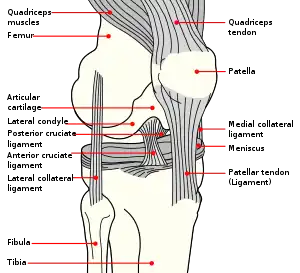

Structure

The knee is a modified hinge joint, a type of synovial joint, which is composed of three functional compartments: the patellofemoral articulation, consisting of the patella, or "kneecap", and the patellar groove on the front of the femur through which it slides; and the medial and lateral tibiofemoral articulations linking the femur, or thigh bone, with the tibia, the main bone of the lower leg.[6] The joint is bathed in synovial fluid which is contained inside the synovial membrane called the joint capsule. The posterolateral corner of the knee is an area that has recently been the subject of renewed scrutiny and research.[7]

Ligaments

The ligaments surrounding the knee joint offer stability by limiting movements and, together with the menisci and several bursae, protect the articular capsule.[16]

Intracapsular

The knee is stabilized by a pair of cruciate ligaments. These ligaments are both extrasynovial, intracapsular ligaments.[17] The anterior cruciate ligament (ACL) stretches from the lateral condyle of femur to the anterior intercondylar area.[13] The ACL is critically important because it prevents the tibia from being pushed too far anterior relative to the femur.[13] It is often torn during twisting or bending of the knee.[18] The posterior cruciate ligament (PCL) stretches from medial condyle of femur to the posterior intercondylar area. This ligament prevents posterior displacement of the tibia relative to the femur.[13] Injury to this ligament is uncommon but can occur as a direct result of forced trauma to the ligament.

The patellar ligament connects the patella to the tuberosity of the tibia. It is also occasionally called the patellar tendon because there is no definite separation between the quadriceps tendon (which surrounds the patella) and the area connecting the patella to the tibia. [20] This very strong ligament helps give the patella its mechanical leverage [21] and also functions as a cap for the condyles of the femur. Laterally and medially to the patellar ligament the lateral and medial retinacula connect fibers from the vasti lateralis and medialis muscles to the tibia. Some fibers from the iliotibial tract radiate into the lateral retinaculum and the medial retinaculum receives some transverse fibers arising on the medial femoral epicondyle.[10]: 206

The medial collateral ligament (MCL a.k.a. "tibial") stretches from the medial epicondyle of the femur to the medial tibial condyle. It is composed of three groups of fibers, one stretching between the two bones, and two fused with the medial meniscus. The MCL is partly covered by the pes anserinus and the tendon of the semimembranosus passes under it.[10]: 206 It protects the medial side of the knee from being bent open by a stress applied to the lateral side of the knee (a valgus force).[10]: 206

The lateral collateral ligament (LCL a.k.a. "fibular") stretches from the lateral epicondyle of the femur to the head of fibula. It is separate from both the joint capsule and the lateral meniscus.[10]: 206 It protects the lateral side from an inside bending force (a varus force). The anterolateral ligament (ALL) is situated in front of the LCL.

Illustrations

Anterior and lateral view of knee.

Anterior view of knee.